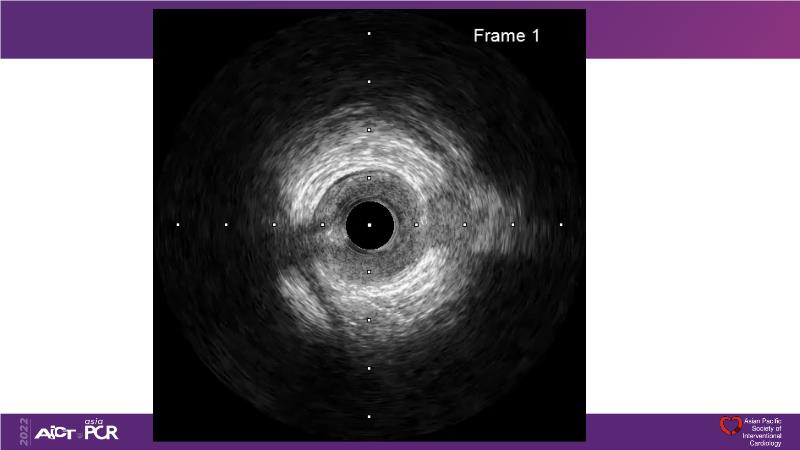

Cracking calcium: best practices to integrate intravascular lithotripsy into your calcium management algorithm

With this session, keep up to date on the evidence, trials and outcome data for intravascular lithotripsy in severely calcified lesions. Learn how to use this technique in real-world patients and understand its role in the treatment algorithm for severely calcified coronary lesions.

- To know the evidence, trials and outcome data for intravascular lithotripsy in severely calcified lesions

- To learn how to use intravascular lithotripsy in real-world patients with severely calcified coronary lesions